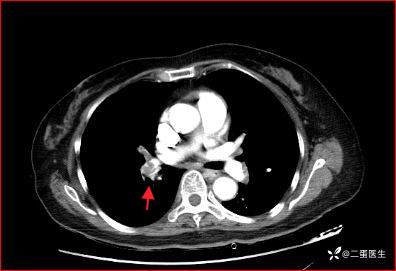

结合患者症状、体征及辅助检查结果,诊断考虑急性肺栓塞,急诊肺动脉CT血管造影(CTPA)提示右肺主干、双肺叶及段动脉内多发充盈缺损,肺栓塞诊断明确。

右肺主干、双肺叶及段动脉内多发充盈缺损